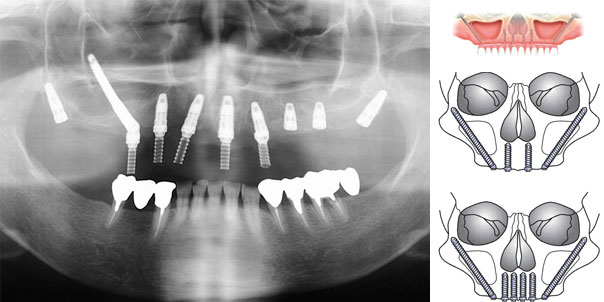

ContáctenosImplantes cigomáticos

El desarrollo de los implantes Cigomáticos representan una excelente alternativa para la rehabilitación total o unilateral del maxilar severamente atrófico, con solo un procedimiento quirúrgico y sin necesidad de injertos óseos, levantamientos de piso de seno , entre otros procedimientos; reduciendo costos, tiempo y visitas al profesional.

Estos largos implantes son anclados en el maxilar y en el denso cigoma, con la colocación inmediata en el mismo acto quirúrgico de una prótesis inmediata temporaria hasta que la restauración definitiva este lista, una vez que se han alcanzado criterios de estética y función.

La principal ventaja de los Implantes Cigomáticos sobre los levantamientos de piso de seno maxilar son la corta duración del procedimiento y las altas tasas de éxito de la técnica, volviéndola más predecible que los injertos óseos.

Si usted es un paciente insatisfecho con su prótesis removible superior, debería considerar esta opción para recobrar en cortas sesiones la estética y función perdidas.

Están también indicados para reconstrucciones de maxilares y mandíbula luego de cirugías por tumores, traumas graves, grandes pérdidas de continuidad, etc.